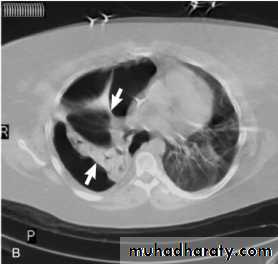

Nodular (coin) lesion in the left upper lung with irregular edge (most probably cancinoma